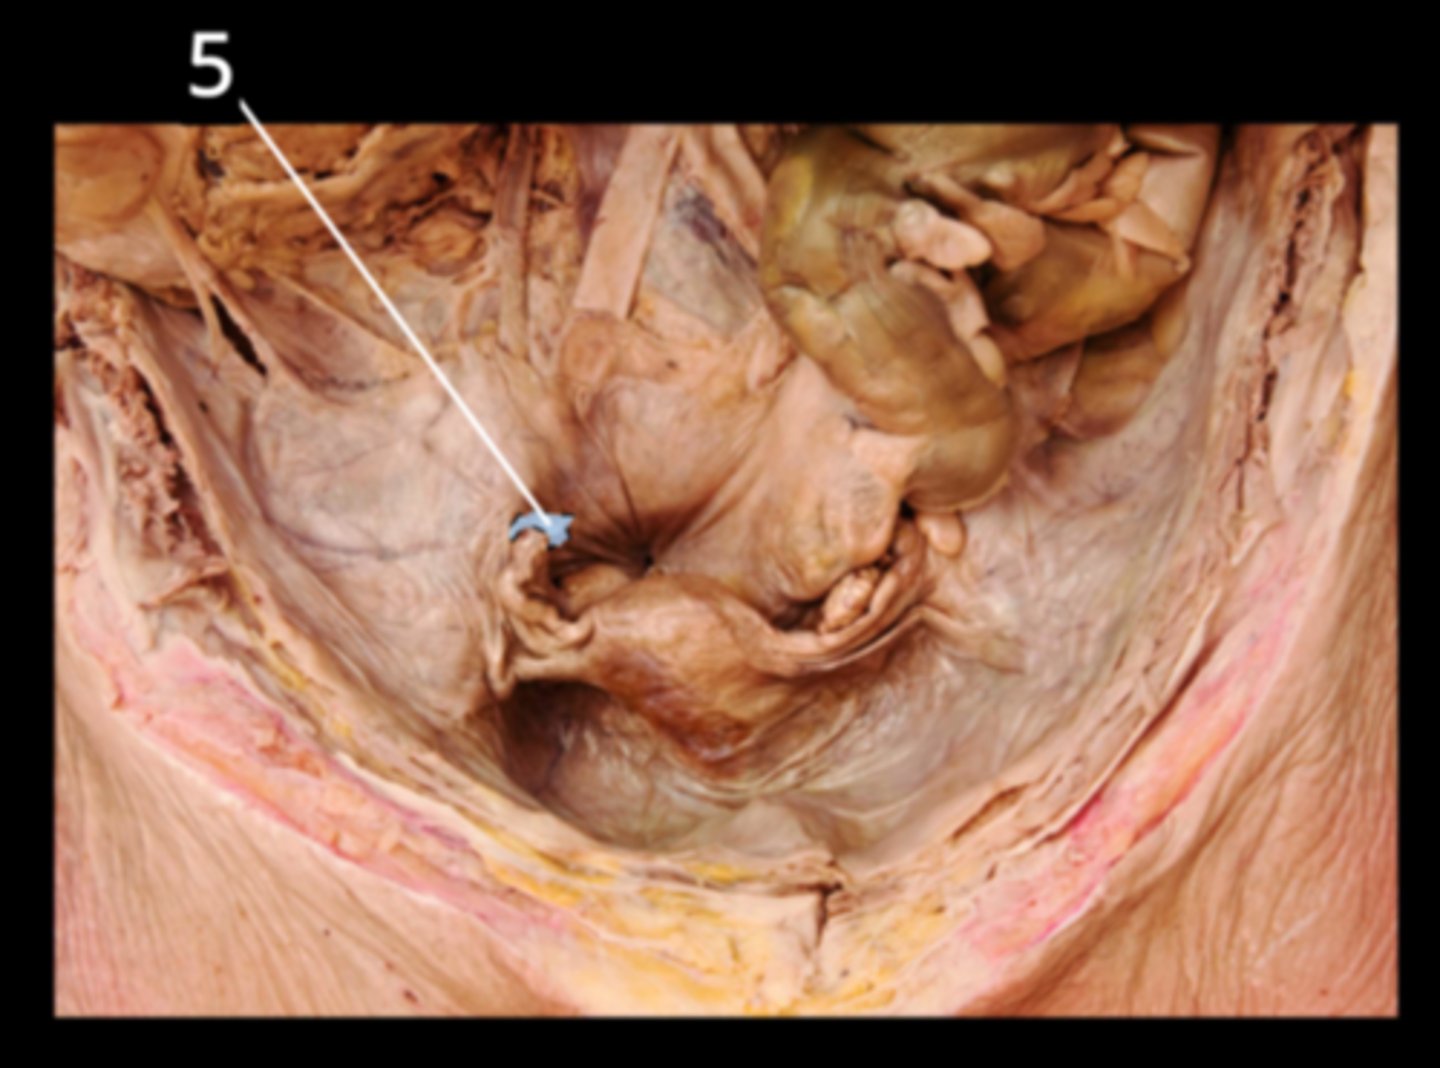

Fatty Appendices